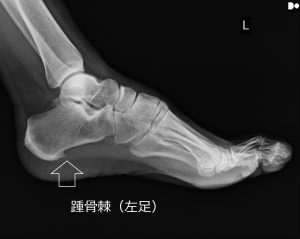

パンプスと踵骨棘・足底腱膜炎 動画

パンプと足底腱膜炎 レントゲンデーターのDVDを整形外科から入手して相談に来られた 「踵の痛み(足底腱膜炎)」との事だったがレントゲンのデーターを見ると『踵骨棘』がくっきり写っている これでは鎮痛剤では効き目がないだろう […]